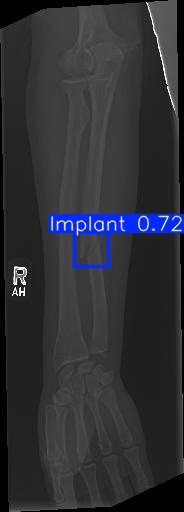

Bone 이미지 데이터 350장 중 Fracture 이미지 50장, Implant 이미지 50장, Bone 이미지 50장을 선별했다.

train과 val은 라벨링을 해야한다. 어제 라벨링을 했었지만, Fracture는 좀 넓게 잡고, Implant는 최대한 여러개로 쪼개는 느낌으로 라벨링을 다시했다.

20251204_01 predict

class 이름을 반대로 해뒀다...

| conf | 0.3 | 원래 0.9였는데 어제 결과가 너무 안 나와서 0.5로 바꿨다가 다시 0.3으로 바꿨다 |